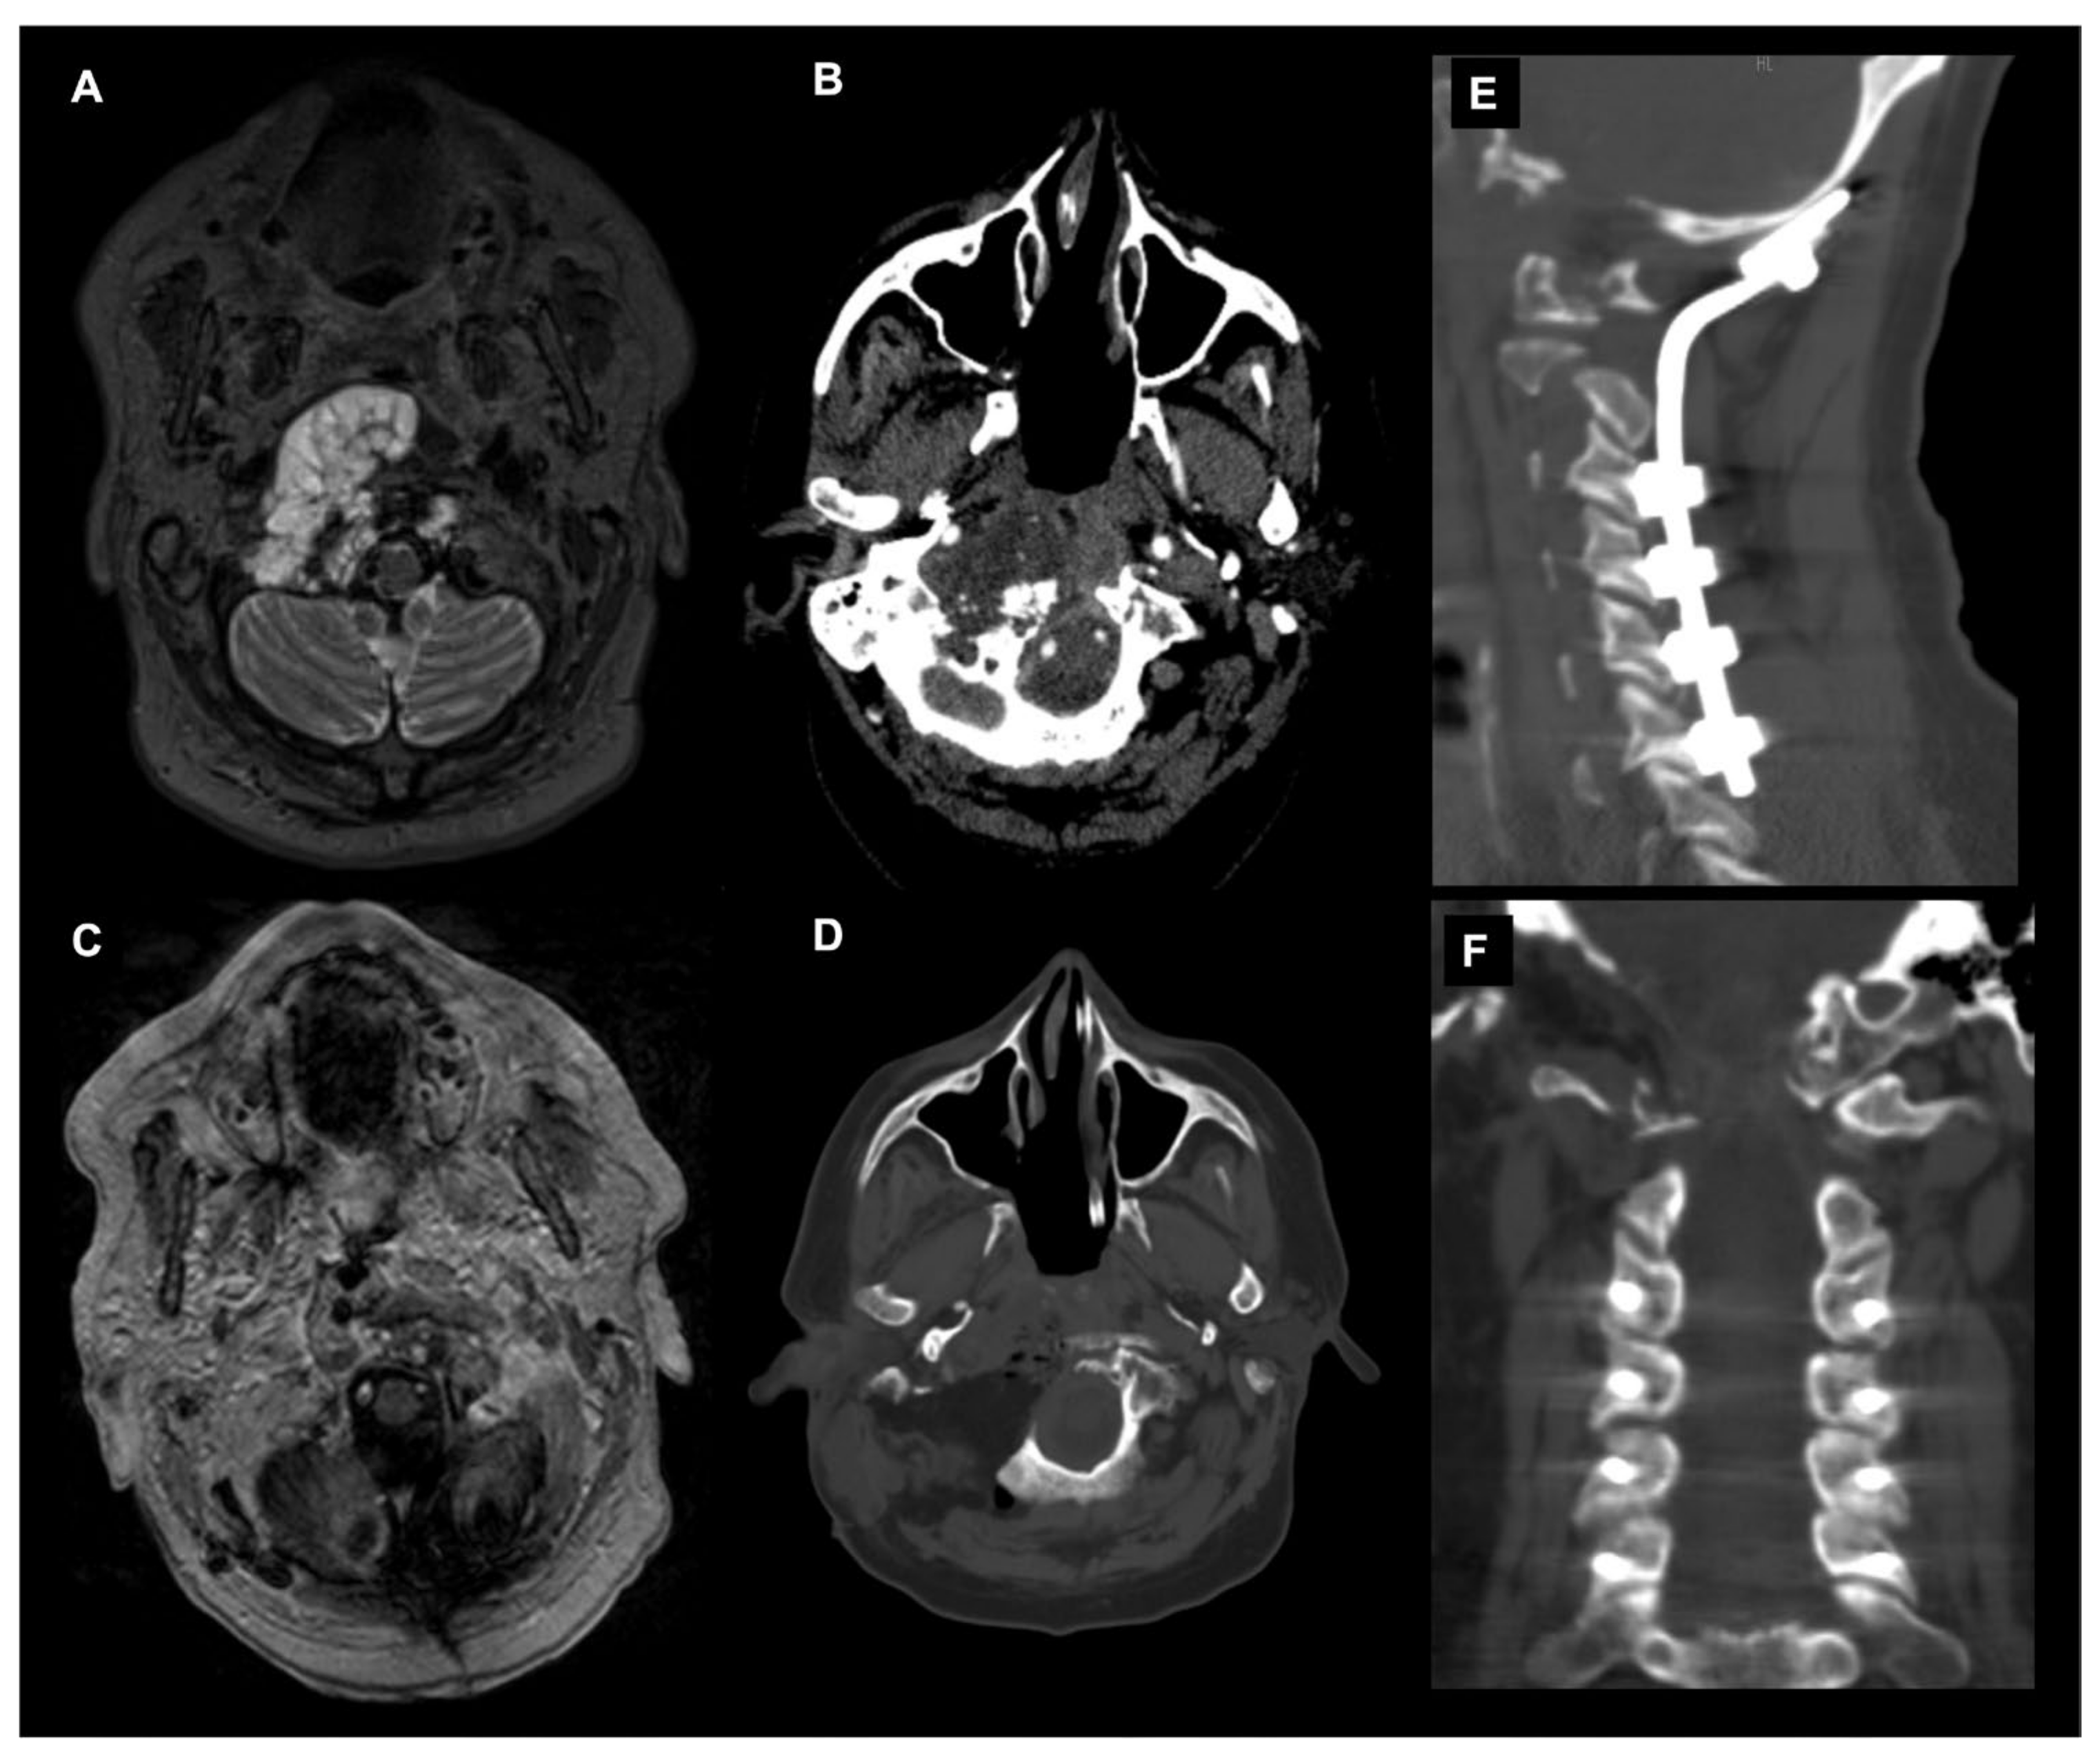

The endoscopic endonasal approach (EEA) to the craniovertebral junction (CVJ) is a minimally invasive surgical technique that allows for access to the CVJ through the nasal cavity (Figure 4).

Figure 4.

Endoscopic endonasal approach (EEA) to a CVJ chordoma. Sagittal (A) and axial (B) T1-weighted images after contrast injection showing a craniovertebral junction chordoma invading the C1 anterior arch, transverse ligament and tip of the odontoid. The patient underwent a gross total removal through an EEA. Postoperative sagittal (C) and axial (D) T1-weighted images after contrast injection confirmed the entity of resection and the integrity of C1-C2 joint. (E) Axial CT scan showing the occipital condyle integrity >90%. Dynamic cervical spine CT scans in maximal extension (F) and flexion (G) showing no abnormal movements and excluding any postoperative CVJ instability.

This approach has been used to treat a variety of conditions affecting the CVJ, including tumors, congenital anomalies and trauma. One of the advantages of the EEA is that it avoids the need for a large incision in the neck or skull, which can lead to less pain, a faster recovery and improved cosmetic outcomes [89,90,91]. Several surgical advantages have been attributed to the EEA in comparison to classical craniotomy or transfacial microsurgical techniques, and they have showed a reduced rate of morbidity and mortality [20,92]. In 2005, Kassam was the first neurosurgeon to use this technique to perform an odontoidectomy [93]. Subsequently, the pioneering work of the Pittsburgh group has been followed by numerous case reports and clinical series that all showed a reduction in the mortality rate and morbidity compared to the classic transoral approach [94,95,96,97]. The main advantages of the EEA to the craniovertebral junction derive from the surgical angle of attack and the surgical incision located at the level of the nasopharynx rather than the oropharynx. The nose and paranasal sinuses provide excellent rostral access and a rostrocaudal angle of attack for the treatment of most pathologies affecting this anatomical region; this is particularly true in patients with basilar invagination or when the odontoid has ascended upwards [98].

The foramen magnum and the superior portion of the cervical spine are located immediately behind the nasopharynx, which can be reached easily and directly through the nasal corridor. The nasopharynx has a significantly reduced proportion of virulent bacterial flora and neural plexuses that coordinate swallowing relative to the oropharynx [99]. The palate is never affected by the approach since the rostrocaudal angle of attack is parallel to that of the soft palate, and thus it does not require its transgression. The angle of approach and the caudal limit of access of the EEA to the CVJ is determined by the rhinopalatine line [100,101]. The lateral exposure of the EEA is limited by the parapharyngeal internal carotids and the jugular foramen. The transnasopharynx–transodontoid approach is an extension of the transclival approach. This approach can, however, be performed independently with preservation of the clivus since, in most cases, the pathology is confined to the level of the cervical spine; moreover, the exposure of the sphenoid sinus is not always required [102,103,104]. Furthermore, the possibility of stabilizing the CVJ through the use of transarticular screws positioned endoscopically via the endonasal have been described in anatomical studies [105,106]. In some situations, lateral exposure at the level of the foramen magnum is required [9]. This is particularly true in conditions affecting the occipital condyle and extending into the jugular foramen. In these situations, it is advisable to provide an appropriate lateral surgical window by removing the occipital condyle and partially resectioning the Eustachian tube. The reaming process of the occipital condyle can be performed until the hypoglossal canal is exposed. Careful neurophysiological monitoring of the cranial nerves is therefore essential to prevent the risk of deficits and to maintain the function of the hypoglossal nerve intact. If the medial occipital condylectomy is unilateral, by keeping the contralateral alar ligament intact, there is no risk of craniovertebral instability.